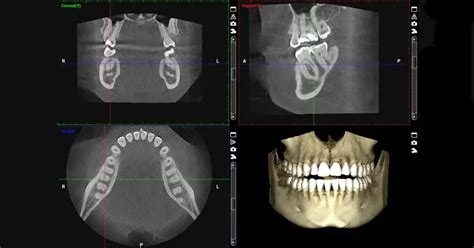

Esquema de la tomografía computarizada de haz cónico (CBCT)

Ejemplo de imagen obtenida mediante TAC Dental